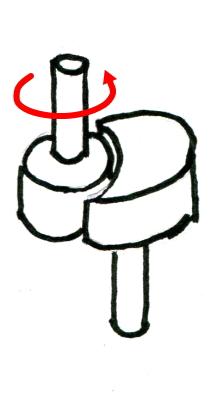

車軸関節

| 軸を保った回旋のみ可能な1軸関節。環軸関節、遠位橈尺関節、近位橈尺関節。 |